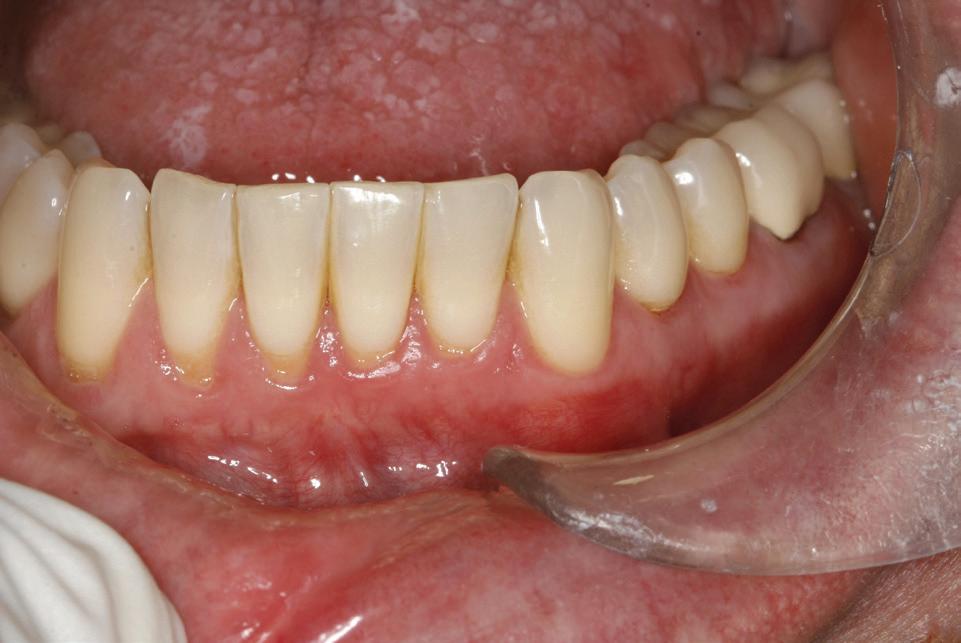

6, 7. Utilizarea lamboului repoziționat apical pentru a gestiona caninii bilaterali cu impactare facială. După expunere, s-a practicat și frenectomia și au fost plasate bracketuri bilaterale (fig. 6). S-a realizat tracțiunea ortodontică, ce a permis poziționarea corespunzătoare a ambilor canini pe arcada superioară (fig. 7)

apoi direcționarea vestibulară a caninului (fig. 8, 9).